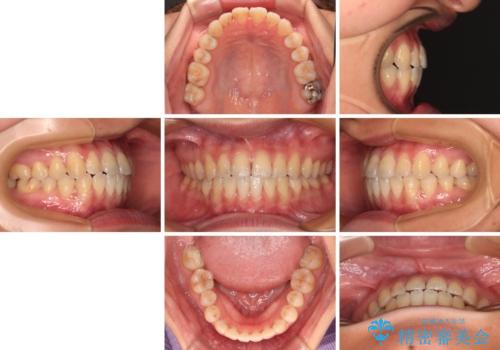

前歯のクロスバイトを治したい ワイヤー装置による矯正治療

- 前歯の反対咬合を気にして来院された患者様です。

クロスバイト改善まではスムーズに進みましたが、その後は強い舌の突出癖によりオープンバイトの期間が長く続きました。

舌のトレーニングをしっかりと実施してもらい、何とか仕上げることができました。